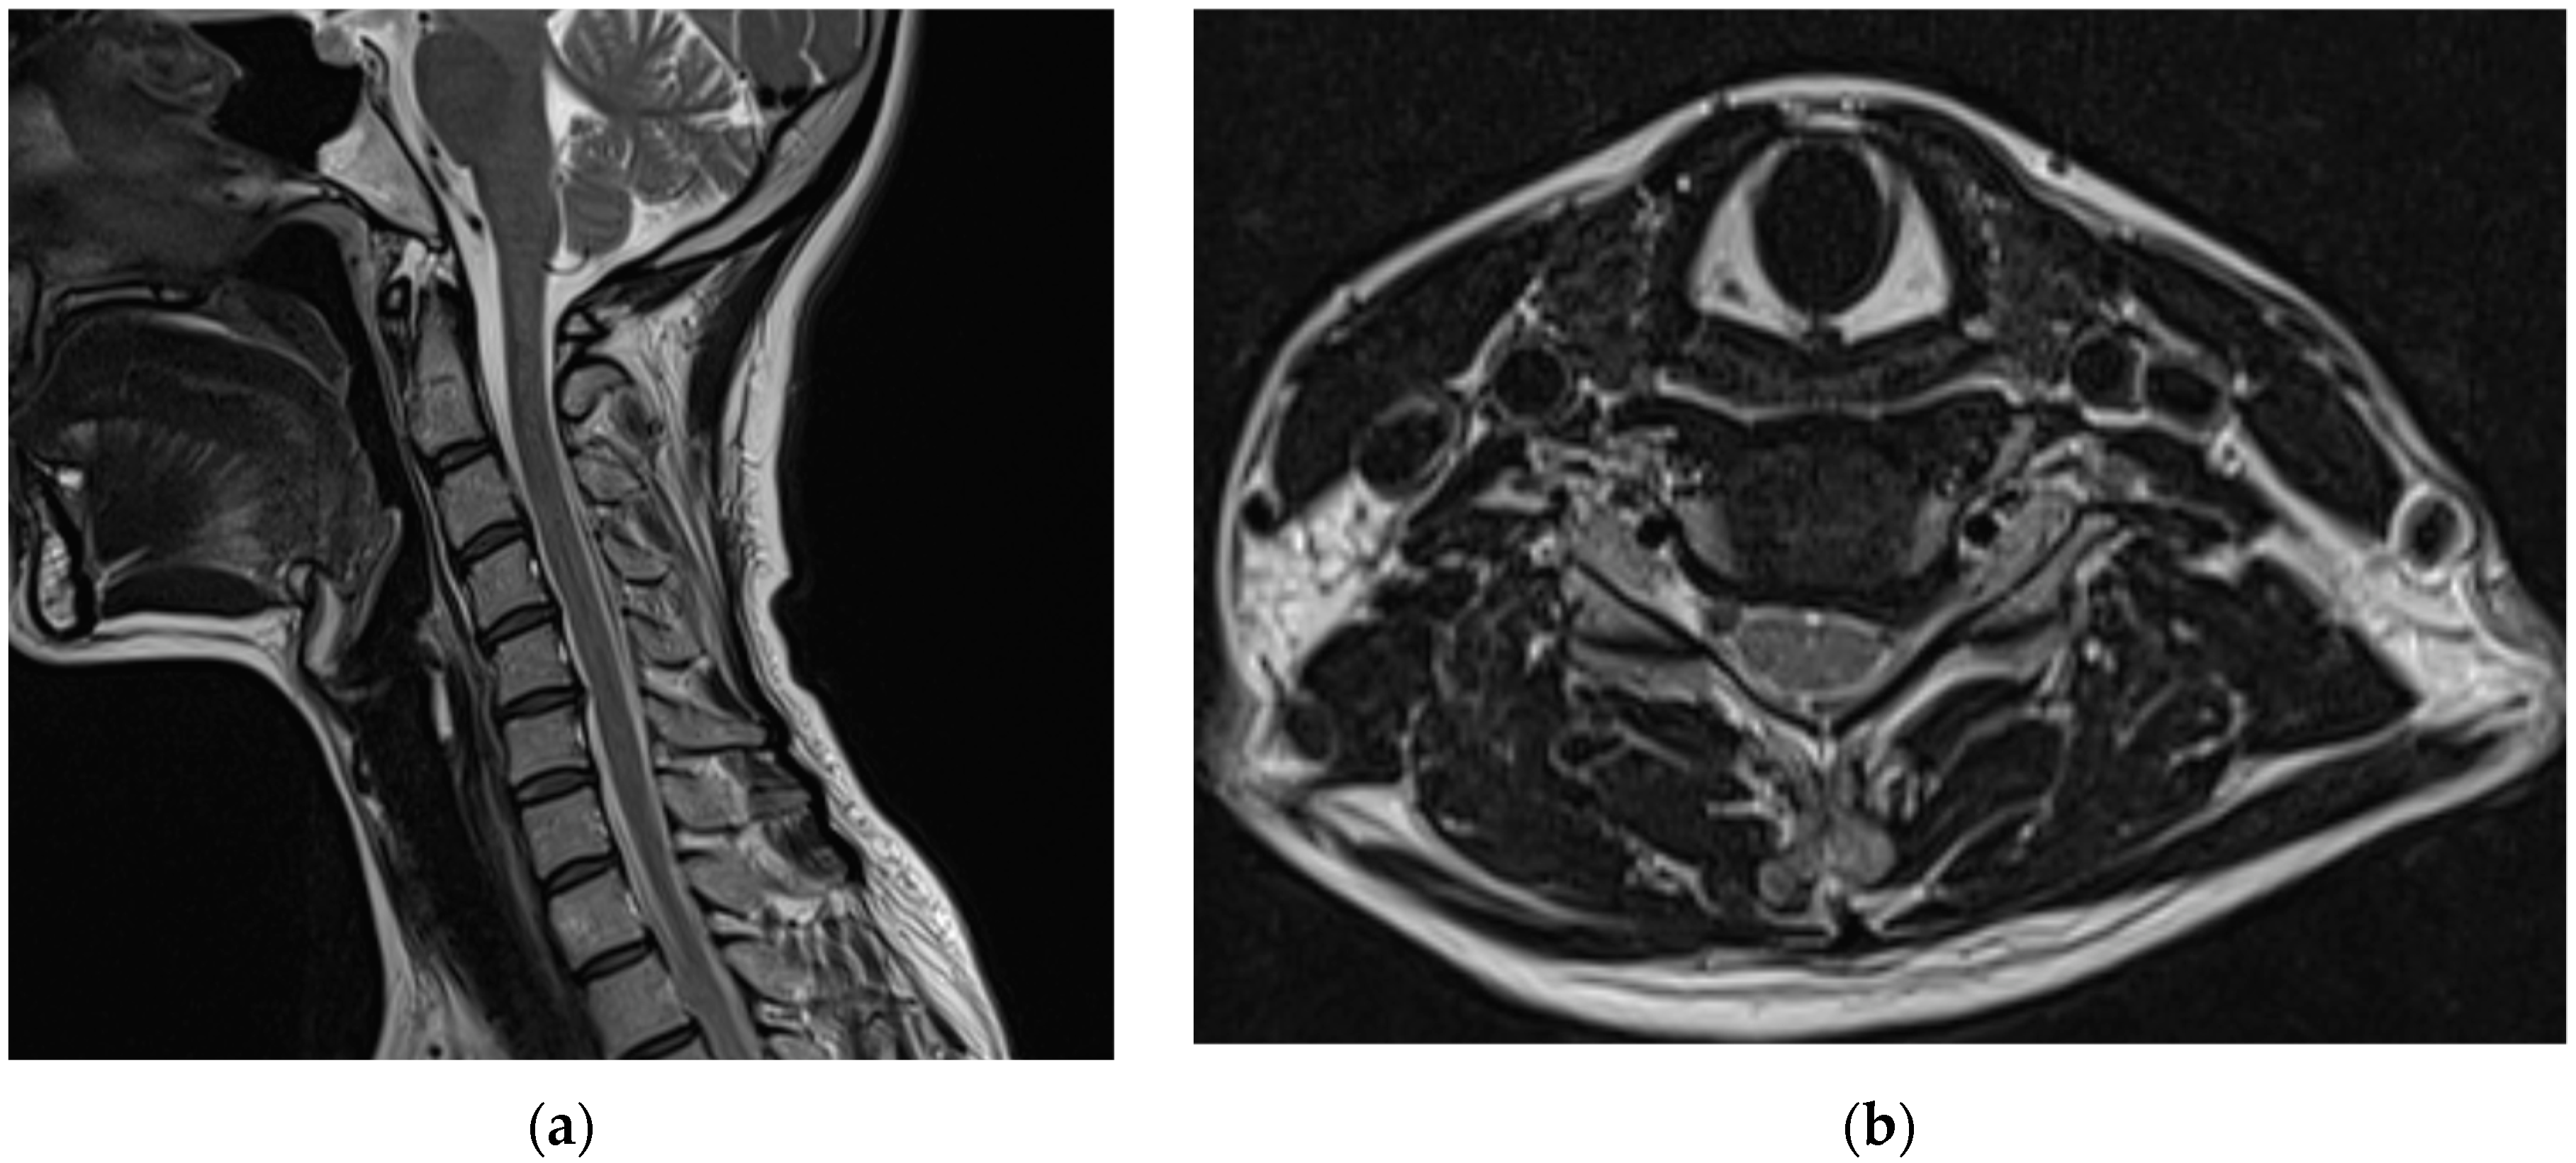

Before visiting our hospital, a 35-year-old woman with no specific medical history visited a spine hospital complaining of posterior neck pain radiating to the left upper arm. These symptoms appeared 6 months before she was admitted at the spinal hospital and had worsened to a Visual Analog Scale (VAS) score of 6 at the time of admission. No motor weakness or sensory changes were observed upon physical examination at the time of admission. However, numbness was observed in the left arm during the Spurling test. Magnetic resonance imaging (MRI) of the cervical spine showed a herniated intervertebral disc at the C5/6 level and left C6 nerve impingement due to left foraminal extrusion (Figure 1).

Figure 1.

Cervical spine magnetic resonance images obtained before the procedure. A herniated intervertebral disc at the C5/6 level and left C6 nerve impingement due to a left foraminal extrusion are observable on the (a) T2-weighted sagittal image and (b) T2-weighted axial image of the C5/6 level.